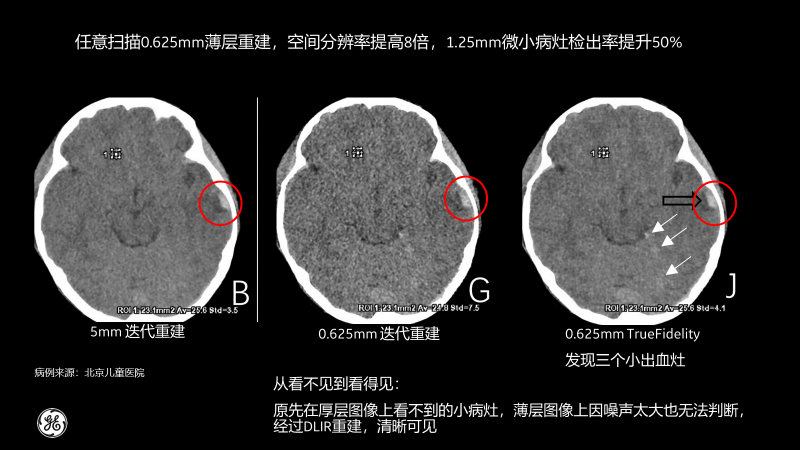

相比傳統(tǒng)CT圖像對腹部檢查一般都選擇5mm厚層重建,TrueFidelity可對任意體型任意部位的檢查進行0.625mm的薄層圖像重建,真實還原圖像的解剖細節(jié)和紋理,提高微小病灶的發(fā)現(xiàn)幾率,有助于早診早治,極大提高醫(yī)生的診斷信心。

北京兒童醫(yī)院的測試病例也顯示,經過TrueFidelity,任意掃描0.625mm薄層重建,空間分辨率能提高8倍,1.25mm微小病灶檢出率提升50%,最終額外發(fā)現(xiàn)了3個之前看不到的微小病灶。